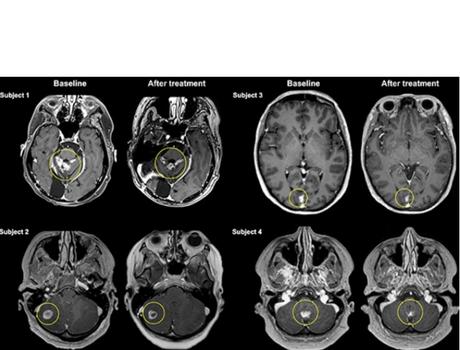

Il s’agit précisément de la publication de résultats préliminaires, chez 4 patientes de l’essai mené au total auprès de 10 participantes atteintes de cancer du sein métastatique, ou cancer du sein de stade IV, un type de cancer qui s’il prend naissance dans le sein s’est propagé au cerveau, aux os, au foie ou à d’autres organes. Les traitements actuels des métastases cérébrales du cancer du sein comprennent la neurochirurgie ouverte, la radiothérapie et la chimiothérapie. Cependant, la chirurgie et la radiothérapie sont souvent limitées par l’emplacement et le nombre de métastases cérébrales.

Ultrasons focalisés = plus d’efficacité : c’est la conclusion de cette analyse préliminaire, de l’efficacité du traitement, de l’évolution de la taille des tumeurs (soit une réduction moyenne de 21 %). Une réduction prometteuse de la taille des tumeurs mais qui doit encore être interprétée avec prudence dans l’attente de recherches supplémentaires.